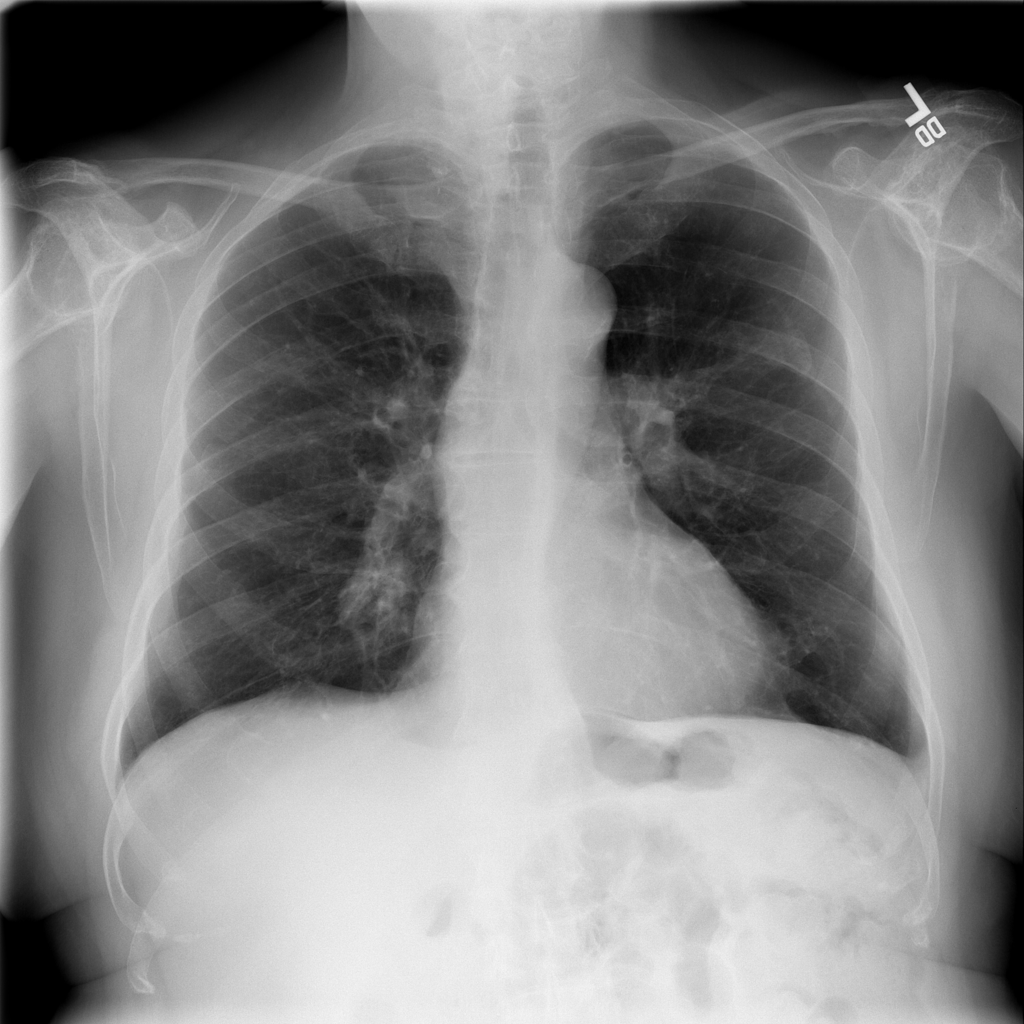

PAT-4639 · IMG-024Mass

PAT-4639 · IMG-024

AP